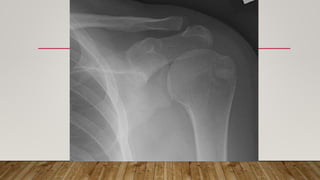

This document discusses radiology and the use of x-rays. It begins with an introduction to radiology and x-rays, noting their importance as the "father of medical investigations." It then discusses anatomy as seen on radiographs and whether x-rays are enough. The document goes on to compare gross views to radiological views, noting what each can and cannot show. It highlights important figures in the development of radiology, from x-rays to CT, MRI, and ultrasound. Specific anatomical structures visible on upper and lower limb x-rays are listed. The document concludes by discussing how pathologies appear on x-rays and the importance of clinical history and knowledge when interpreting radiological images.